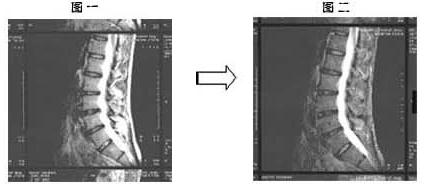

约一年前因突然腰关节痛和坐骨神经痛导致无法行动,在整型外科诊断出罹患腰椎间盘突出症。之后,接受牵引治疗,服用抗炎药物等治疗方法,但始终未见成效。在那样情况下,该病患只好放弃汽车工厂的工作,办理停职一年。之后,2003年3月到本院接受诊疗,利用MRI(核磁共振图)(参看图一)诊断出腰椎间盘突出症。在确认该病患之前所接受的治疗经过后,得到患者本人同意,开始改以每日服用7.5g 百傲鲨锯峰齿鲛软骨粉末的治疗方式。

2003年3月初诊时的MRI(核磁共振图)(参看图一)与2004年4月的MRI(核磁共振图)(参看图二)相比,可清楚看到腰椎间盘突出症状,已有明显的改善。

椎间盘的场合,用软骨再生来表达不太合适,但可知软骨已恢复了正常弹性。而且,服用一个月后腰关节痛和坐骨神经痛感减少,两个月后疼痛状况完全消失,由此可得知百傲鲨对腰椎间盘突出症,具有消除坐骨神经痛和腰腿关节痛的效果。